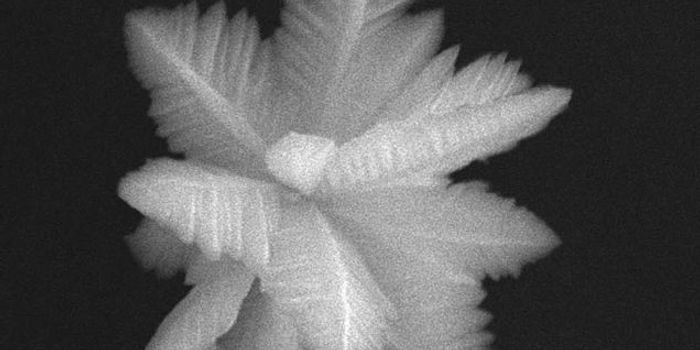

AUG 17, 2016CancerBy combining nanotechnology and the wonderful world of microbiology, Canadian scientists have created something truly un ...